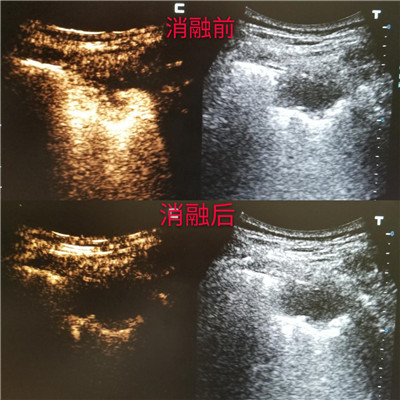

超声造影作为目前最先进的超声成像技术,能够提供比普通超声及彩色多普勒超声更丰富、更明确的诊断信息。它在常规超声检查的基础上,通过静脉注射超声造影剂,来增强人体的血流信号,实时动态地观察正常脏器和肿块的血流灌注情况,提高超声诊断的特异性和敏感性。微波肿瘤消融术是的肿瘤微创治疗技术,它的原理使局部肿瘤组织凝固性坏死,最终形成液化灶或纤维化,起到原位灭活肿瘤组织的作用。具有疗效好、创伤小、痛苦小、恢复快、适应症广等优点。大多肺癌微波消融术是在CT引导下进行,但是对于紧贴胸壁的周围型肺癌,超声可以实时清晰显示。而超声造影在微波消融治疗前、中、后应用,可降低穿刺并发症的风险,确定治疗术中监测评价疗效。

超声造影评估微波消融治疗情况